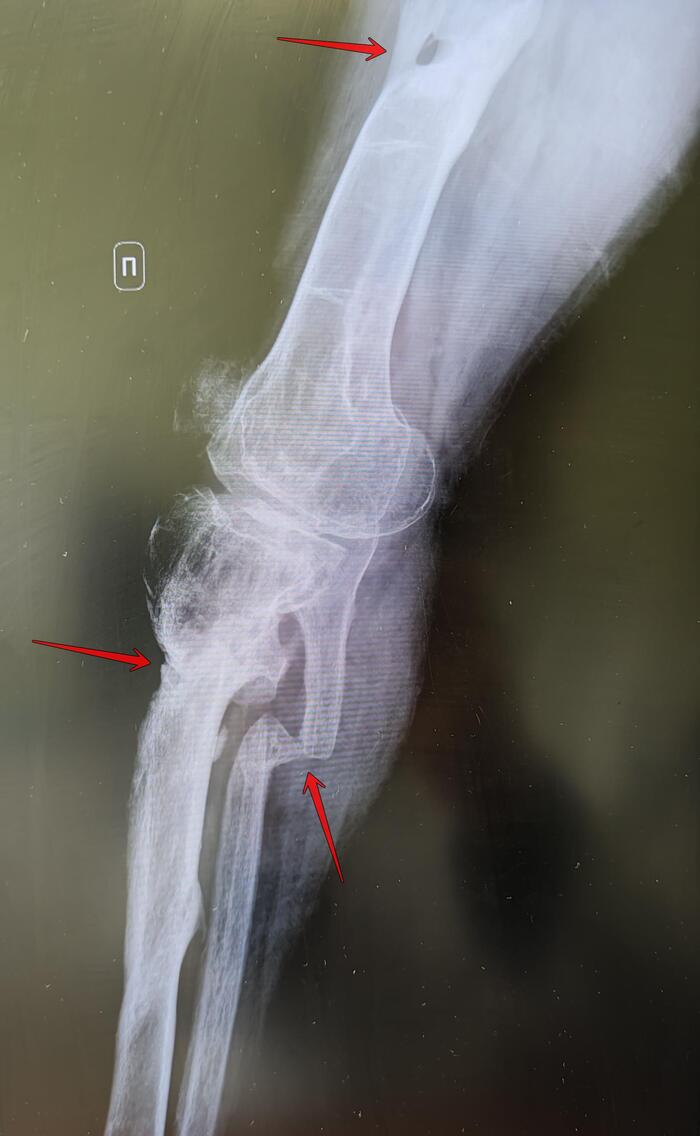

Хронический остеомиелит большеберцовой кости ⁠⁠

Рентгенографическое исследование на ранних сроках позволяет выявить изменение плотности окружающих кость мягких тканей, участки деструкции костной ткани, периостит. На поздних сроках (начиная с 14-ого дня) на рентгенограммах определяются обширные очаги деструкции, линейные, слоистые периостальные наслоения, участки склероза вокруг секвестров и зон деструкции и окружающая эти участки зона остеопороза. В случае посттравматического остеомиелита определяется замедление консолидации отломков. Хронический остеомиелит на рентгенограммах проявляется гиперостозом (и, как следствие, деформацией кости), очагами деструкции кости, окружѐнными зоной склероза; секвестрами, остеопорозом.

Описание к снимкам :На Р-граммах левой большеберцовой кости определяются очаги деструкции: в в/3 с массивным сформированным секвестром 12х1см,в н/3-6х1.5см с формирующимся секвестром, разрежение костной ткани, гиперостоз в в/3,н/3 бедренной кости

Заключение: Признаки хронического остеомиелита левой большеберцовой кости.

Ds: Хронический остеомиелит большеберцовой кости соответствует cт.65в-В, 565 постановления: ограниченно годен к военной службе.